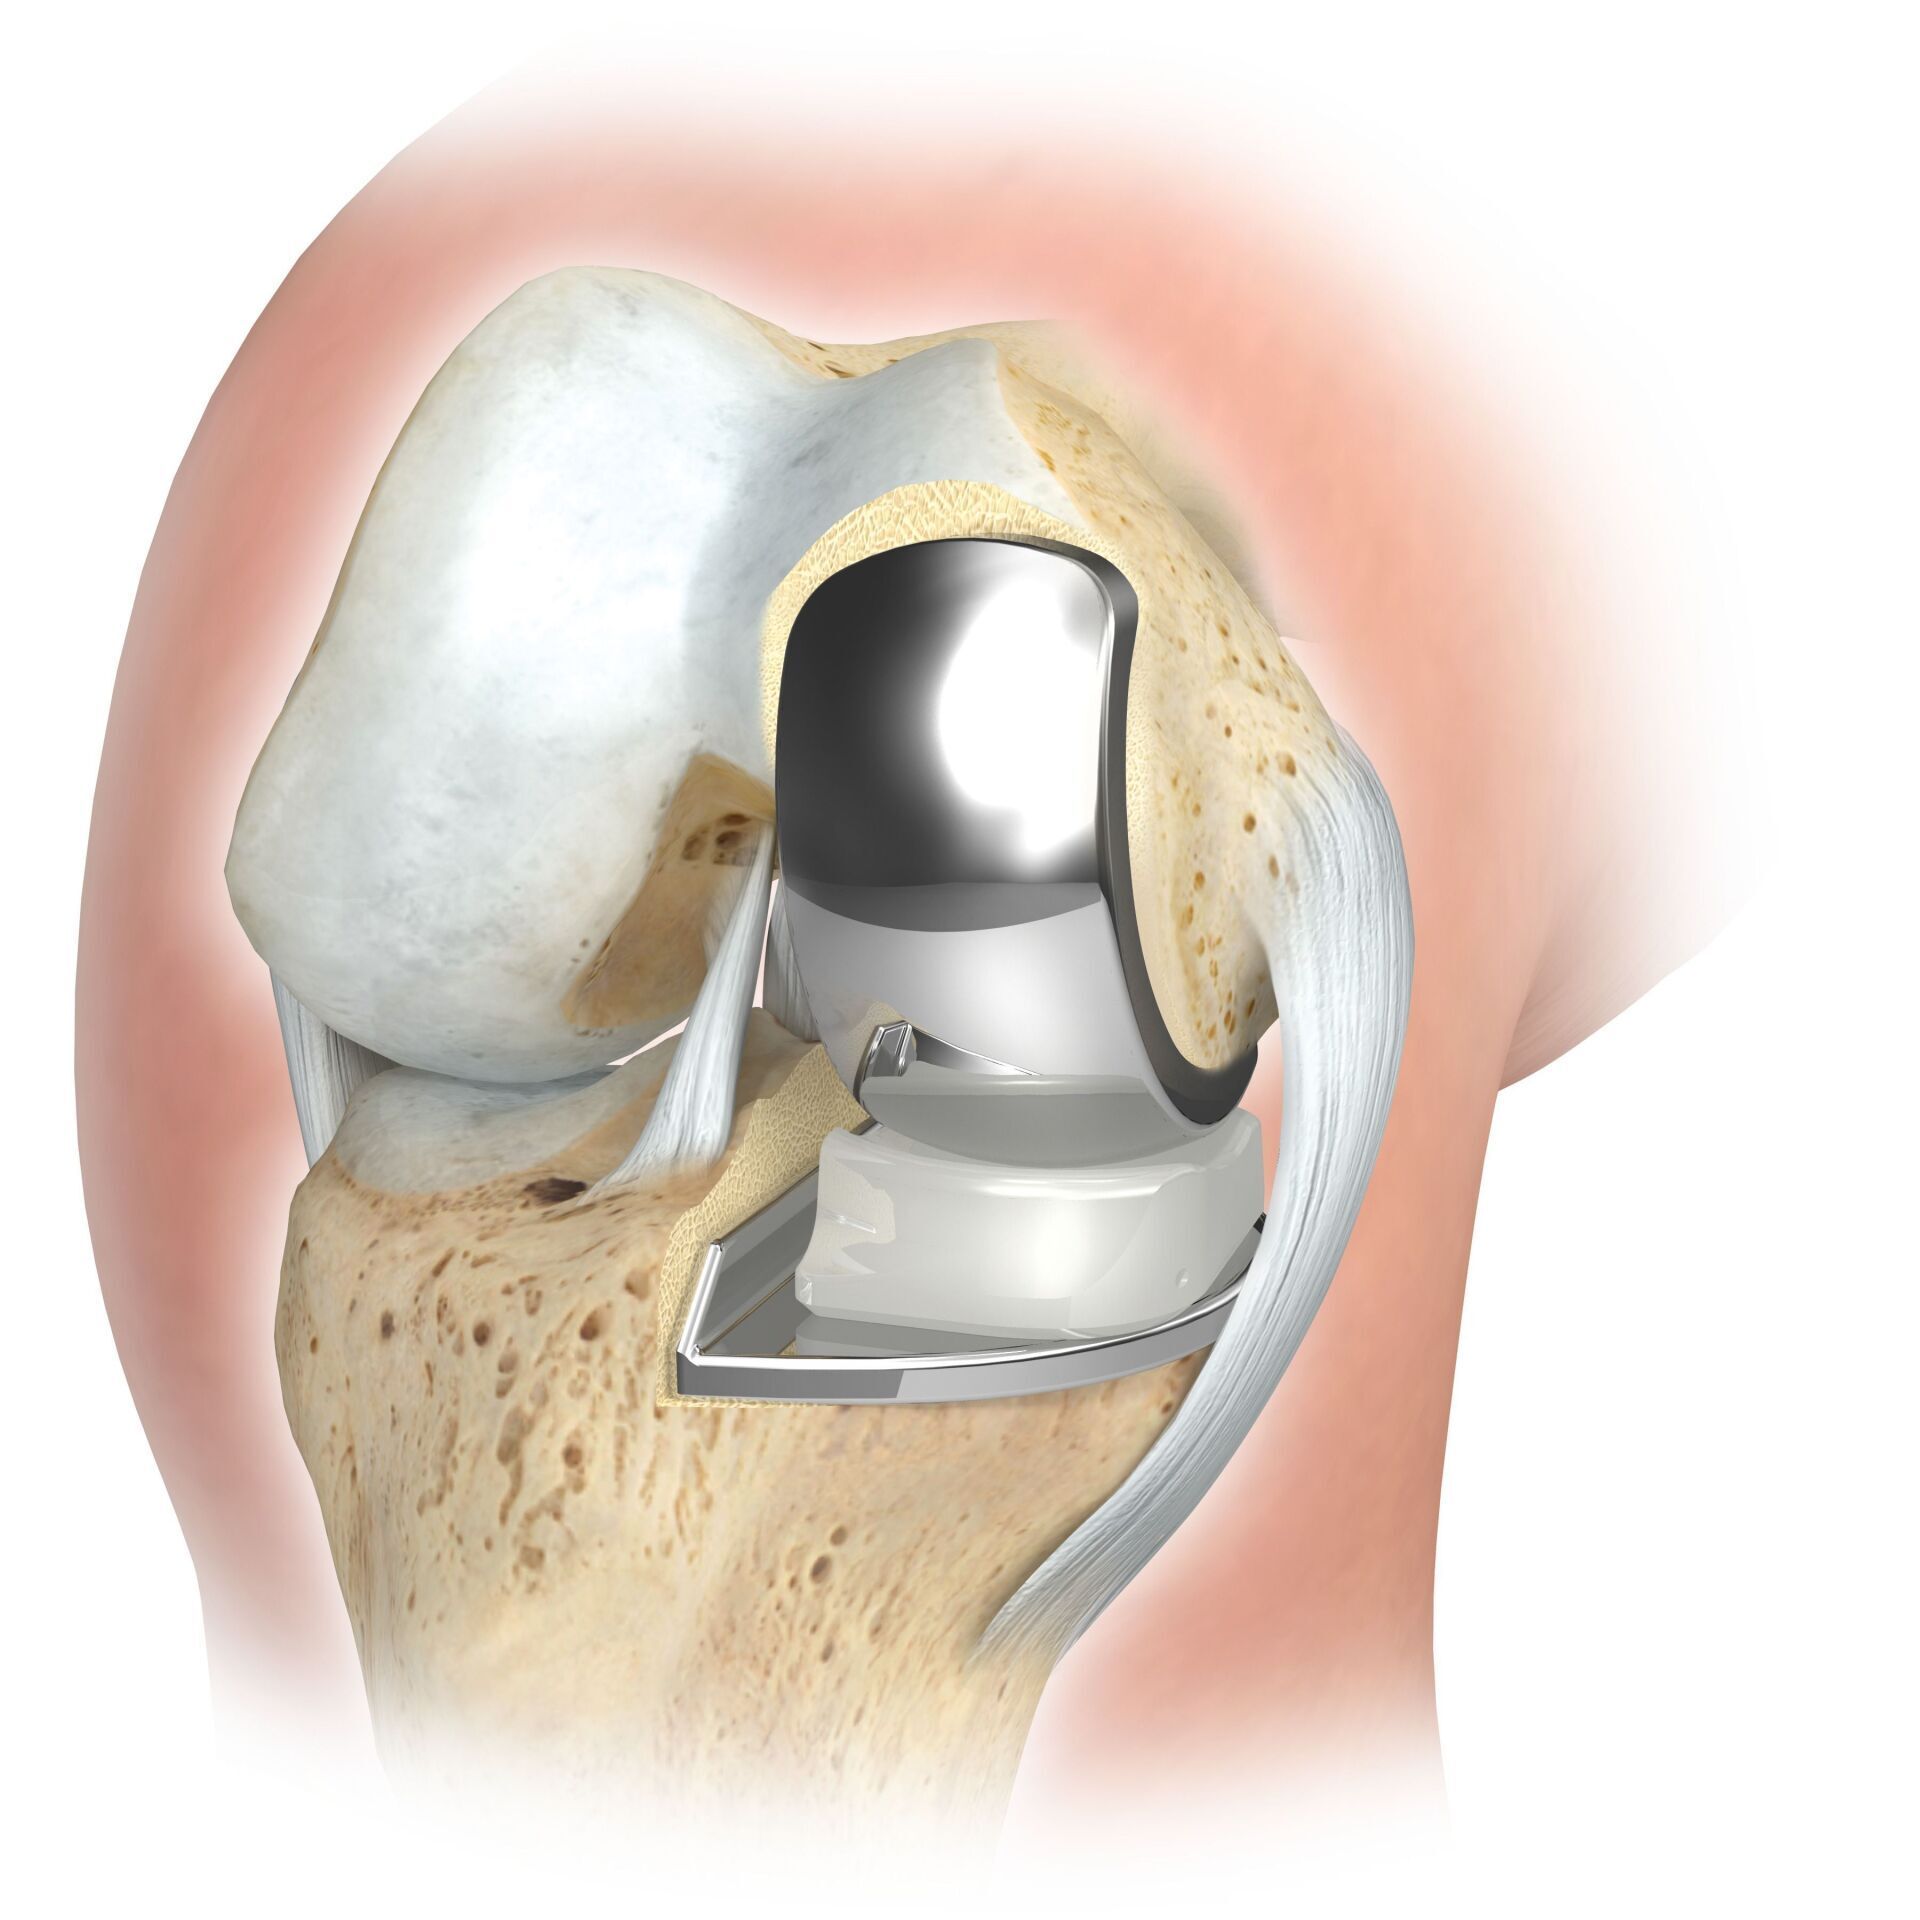

Man spricht bei künstlichen Kniegelenken von Vollprothesen und Teilprothesen. Welche Prothese für Sie in Betracht kommt, Prüfe ich sorgfältig vorher anhand der klinischen Untersuchung, sowie anhand von Röntgenbildern oder MRT-Aufnahmen.

Der künstliche Gelenkersatz ist im fortgeschrittenen Stadium der Arthrose eine sehr erfolgreiche und zuverlässige Behandlungsoption.

Das künstliche Kniegelenk ersetzt die durch die Arthrose zerstörte Knorpeloberfläche. Der darunterliegende Knochen am Oberschenkel und Schienbeinkopf bleibt erhalten. Manche vergleichen ein modernes künstliches Kniegelenk mit einer

Überkronung bei einem Zahn, der genaue Begriff ist der sogenannte

bikondyläre Oberflächenersatz. Zwischen den neuen Oberflächen am Ober- und Unterschenkel befindet sich das sogenannte Inlay aus einem speziell verhärteten weißen Kunststoff, das im Röntgenbild als Abstand zwischen den Metallteilen zu erkennen ist.